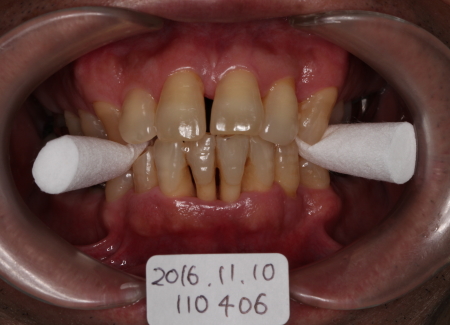

FOP

2016-11-10

主訴:歯牙の動揺